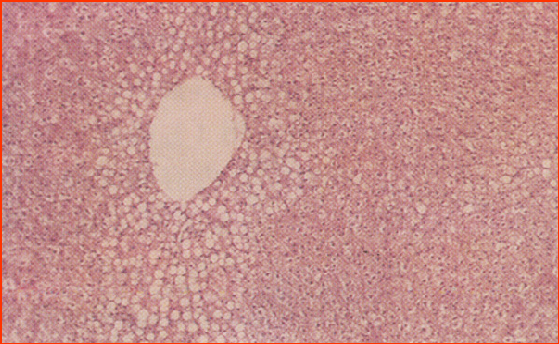

常见营养代谢病防治